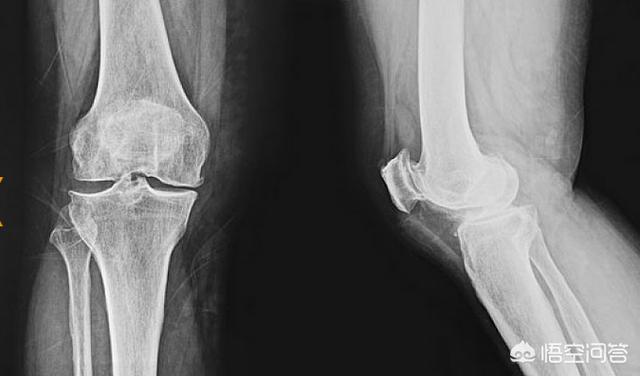

1) Les personnes âgées de plus de 50 ans souffrent d'une usure du cartilage du genou due à la dégénérescence de la fonction articulaire, ce qui induit une douleur dans la partie médiane du genou. Avec le déclin physique des personnes âgées, la fragilité du tissu péripatellaire augmente, la marche dans le processus d'alternance répétée entre les deux jambes, la paroi médiale du genou tire de manière répétée, au-delà de la limite, puis il y a une légère blessure de déchirure et un œdème autour de la blessure. Après des années de choc, le cartilage de la surface articulaire et le cartilage méniscal sont épuisés, formant essentiellement un choc entre le condyle fémoral médial et l'os du condyle tibial médial.

2) Chez les jeunes, la douleur médiane du genou est généralement due à une lésion des ligaments du genou. Les jeunes ne présentent pas de lésions importantes en raison de l'amortissement du cartilage très épais de la surface de l'articulation et du cartilage méniscal. Cliniquement, elle se manifeste par une douleur et un gonflement du côté médial du genou. Malgré la douleur, la radiographie ne révèle aucune modification osseuse.

3. Il existe également une sorte de douleur interne au genou causée par une lésion du ménisque du genou. Le ménisque du genou est une sorte de cartilage situé au milieu de la cuisse et du mollet de l'articulation du genou, qui joue un rôle important dans la transmission de la force de l'articulation du genou. Si le ménisque du genou est endommagé, la force du corps ne peut pas être transmise de manière uniforme à travers l'articulation du genou, ce qui facilite l'apparition prématurée de l'arthrose de l'articulation du genou et provoque des douleurs dans l'articulation du genou. Les lésions méniscales du genou sont le plus souvent observées dans deux cas : tout d'abord, les lésions traumatiques. Les sports sont propices aux lésions du ménisque du genou. Deuxièmement, une lésion dégénérative. Avec l'âge, le ménisque dégénère, se déchire et s'abîme. Les lésions méniscales surviennent souvent en même temps que les lésions ligamentaires du genou.

Les deux symptômes les plus courants d'une lésion du ménisque du genou sont la douleur et le gonflement au niveau du site de la lésion. S'il y a une douleur et un gonflement à l'intérieur du genou, il est probable que vous souffriez d'une lésion du ménisque interne du genou. Un bruit sec dans l'articulation du genou et parfois une sensation de blocage du genou sont souvent observés après une lésion du ménisque interne.